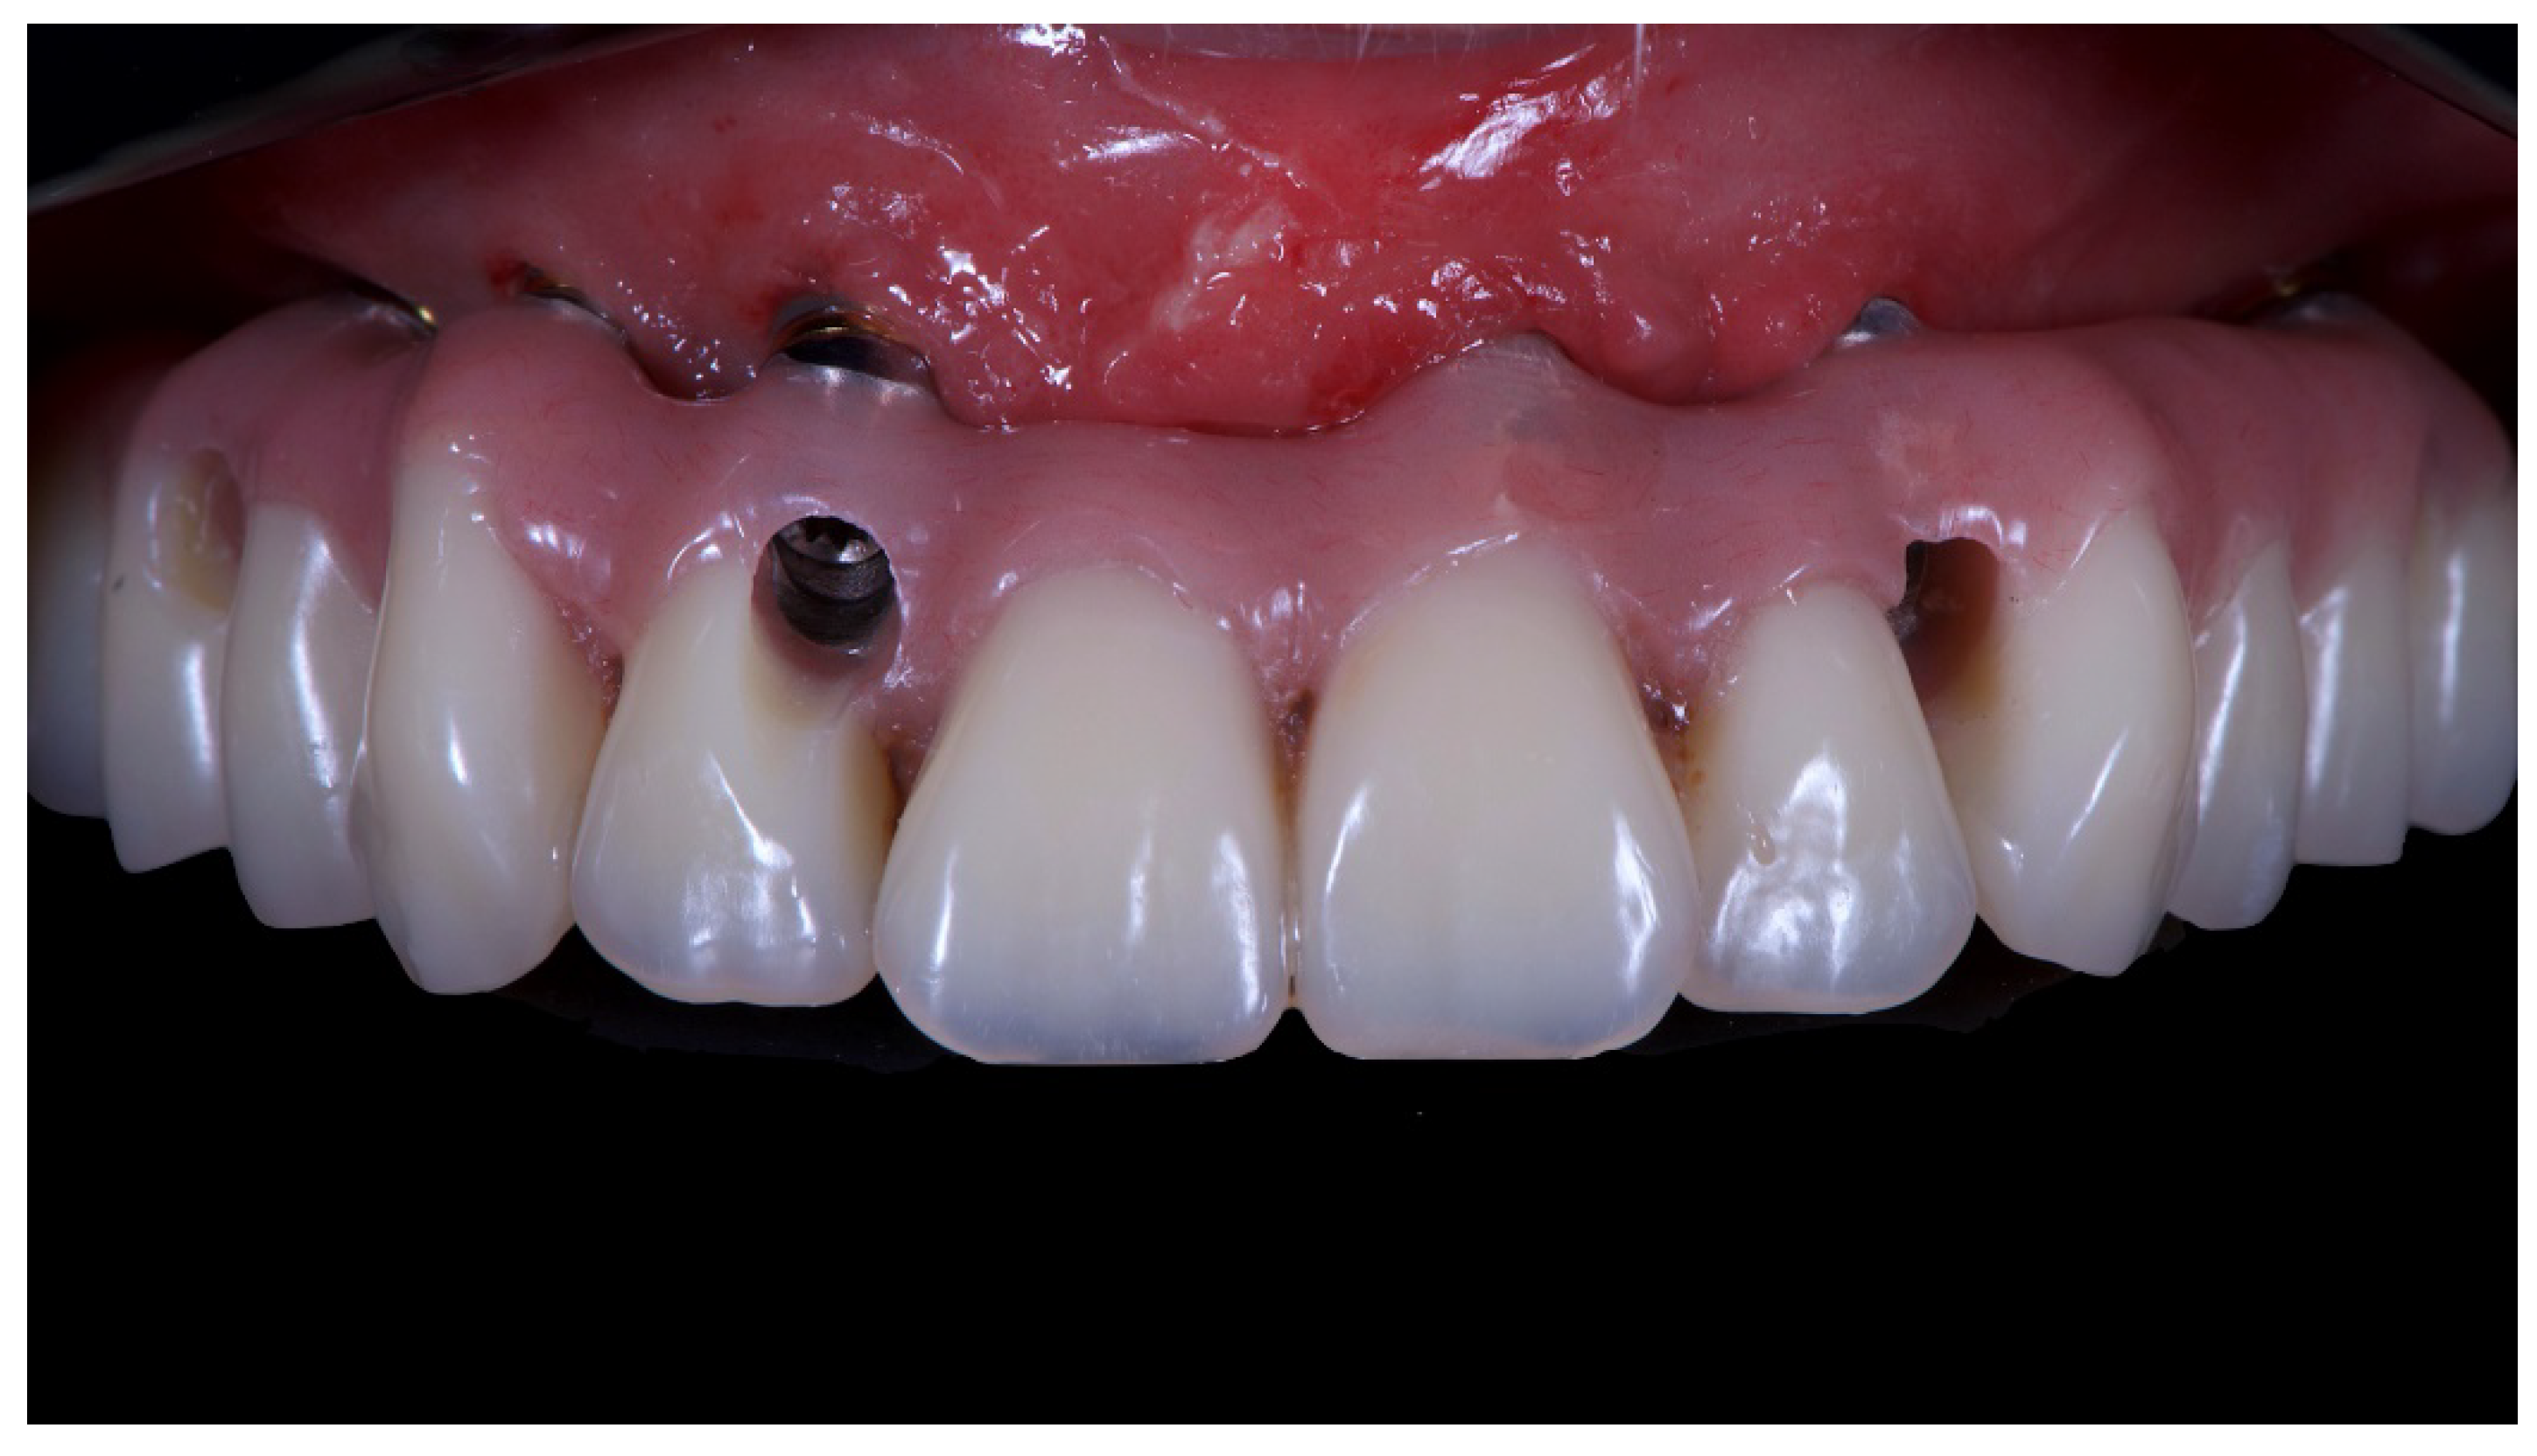

Before definitive impression, multi-unit abutments were unscrewed, the implant connections were cleaned, and six OT Equator Titanium Abutments (Rhein’83, Bologna, Italy) with TiN coating were screwed (Figure 6), according to the manufacturer. Immediately after, the patient received a digital impression (CS 3600 intraoral scanner, Carestream Dental, Milan, Italy), taken at abutment level (Figure 7), using dedicated scan abutments (OT Equator Titanium Scan Abutment, Rhein’83). However, overlapping of the captured images failed to produce an accurate impression, maybe due to the disparallelism of the implant ranging from 65° to 86°. Hence, a prototype model was created and a convention gypsum impression [16] with a customized impression tray was taken at abutment level using conventional impression coping (Titanium Impression Coping, Rhein’83; Figure 8 and Figure 9). Esthetics, phonetics, the occlusal vertical dimension, and the centric relation were verified and approved by both the clinician and the patient (Figure 10 and Figure 11). Only after that, a definitive cast, implant position, and esthetic try-in were digitalized and a CAD/CAM titanium bar (NewAncorvis, Bologna, Italy) was anatomically designed with a dedicated software (Exocad DentalCAD, Exocad, Darmstadt, Germany) by a certified dental technician (MA), according to the prosthetic contours and the implant position. Three projects were created with a three-, two-, or one-piece CAD/CAM titanium bar, respectively (Figure 11b). Each of these projects failed to create an accurate titanium bar able to respect the minimum restorative space required by the prosthetic volume of the tried prosthesis, due to the multiple components involved (attachment system, prosthetic framework, artificial acrylic composite teeth, and pink acrylic base). Hence, a fourth project was created with a CAD/CAM titanium bar designed for a fixed screw-retained restoration, initially excluded due to the implant disparallelism. In order to overcome the undercuts created by the tilted implants, and to produce a passive-fit CAD/CAM titanium bar, abutments with an extragrade system were applied (Figure 11c). Extragrade is a special titanium abutment which has the possibility of entering, even in cases of strong disparallelisms, thanks to its internal design. On a large number of implants (those positioned worse from the point of view of the emergence profile), we cannot put the through screw. In this case, the abutment will be retained by the white Seeger only. The number of abutments without screws was limited to two, according to the manufacturer and considering the overall number of placed implants. Moreover, an angulated screw channel concept was applied to avoid the access hole in the vestibular area of the anterior teeth, moving the access holes in the pink area of the hybrid prosthesis. The fit of the implant bar was clinically and radiographically tested in the patient’s mouth, according to established criteria ([17,18,19]; Figure 12). It was important to position the flat surfaces of the abutment-bar connections in correspondence with the undercut created by the inclination of the implant; the flat surface indicates the location of the extragrade bevel, which allows the framework to overcome the undercuts created by the tilted implants. After that, an interocclusal record was taken in centric relation, and the prosthesis was delivered. The screw-retained fixed complete implant-supported prosthesis was seated in the patient’s mouth using the snap-on function offered served by the Seeger System (Figure 13). Four out of six screws were tightened according to the manufacturer, and the screw-holes were closed using composite pink materials. Finally, the occlusion was adjusted and radiographs were taken. The patient was scheduled for hygiene maintenance and control every 4 months (Figure 14, Figure 15 and Figure 16).

Figure 13.

Final prosthesis mounted. Note the through holes. In two cases, it was compensated with only the Seeger, without a through screw.

Figure 14.

Final prosthesis with composite fillings made with pink and tooth-colored composite.